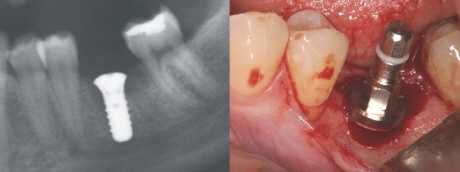

Ausgangssituation

Ein Zahn ist durch eine tiefe Karies verloren gegangen. Die Nachbarzähne sind nahezu unversehrt, nur der letzte Zahn hat eine kleine Füllung (weiß im Röntgenbild). Um weitere Folgeschäden zu vermeiden, entschied sich die Patientin für ein Zahnimplantat.

Implantation

Drei Monate nach der Zahnentfernung wurde in einem kleinen Eingriff ein Zahnimplantat in die Lücke gesetzt. Auf dem Röntgenbild links sieht man das Schraubenimplantat (weiß) und rechts das Zahnimplantat im Mund direkt nach dem Einsetzen. Der Einbringpfosten ist noch auf dem Implantat zu erkennen. Dieser wird abgeschraubt und auf das Implantat für die Einheilzeit eine flache Verschlusskappe aufgeschraubt.